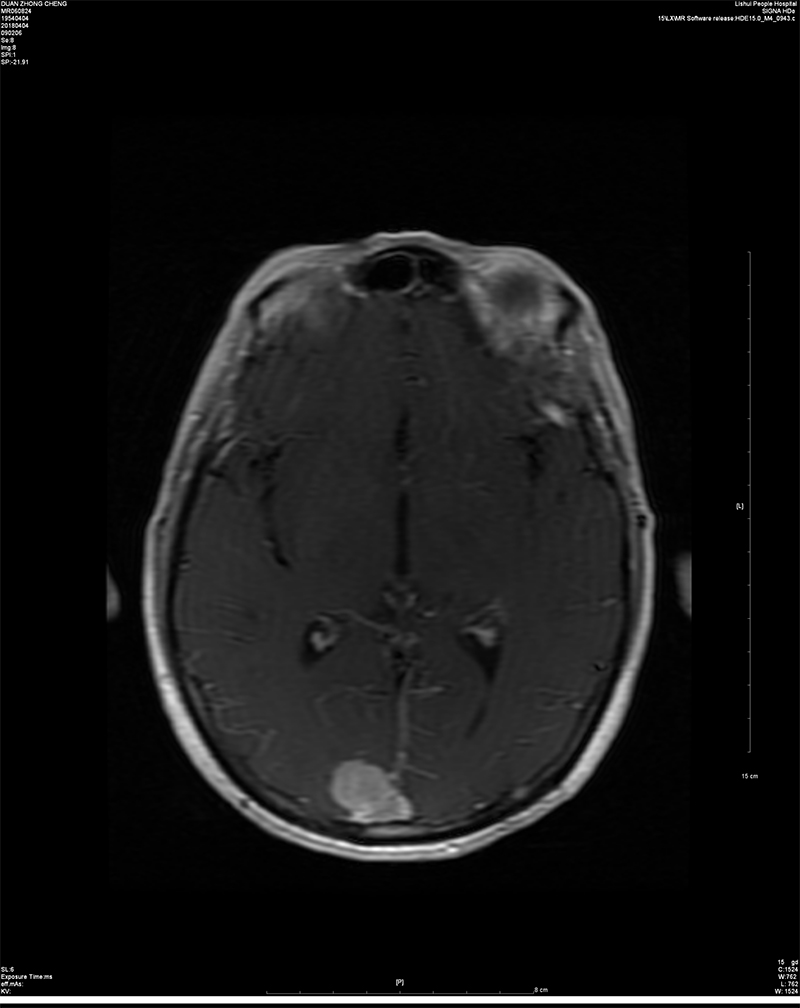

近日,我院神经外科成功完成一例矢状窦旁脑膜瘤切除术。 患者段某,男,64岁,已婚,南京溧水人。因“头晕一周,体检发现颅内占位一小时”入院。入院后经进一步完善检查,术前诊断考虑右侧顶枕部矢状窦旁占位:脑膜瘤可能。矢状窦旁脑膜瘤是肿瘤基底附着在上矢状窦并充满窦角的脑膜瘤。上矢状窦是大脑半球最重要的引流血管,不仅引流大脑半球皮质特别是中央前、后回等重要功能区的静脉血,而且也是脑脊液回流的最主要通道。该部位肿瘤因与上矢状窦及与很多汇入上矢状窦的大脑表面引流静脉关系密切,手术难度大,稍有不慎即可引起血管损伤破裂出血,甚至导致患者死亡等情况的发生,使得很多神经外科医师望而生畏。患者入院后,院长助理、神经外科赵鹏来主任带领全科人员仔细阅片、制定手术方案,科副主任杨平来主任医师、周立田副主任医师精心手术,最终顺利切除肿瘤。上矢状窦及引流静脉保留完好,无并发症发生,目前患者已康复出院。 近年来,神经外科在院领导及科主任的带领下,积极响应区里及院里的号召,刻苦钻研,努力提高医疗技术及服务水平,争创南京市医学重点专科,积极投入到创建三级医院的工作中,以满足我区人民日益增长的就医需求。目前,神经外科不仅能够开展常见的各类脑外伤、脑出血、脑肿瘤、脑积水等手术,同时已具备开展颈动脉内膜剥脱(CEA)及动脉瘤夹闭等特殊类型手术的条件和能力。神经外科将一如既往钻研新技术,以方便患者在家门口就医,提高社会满意度。

术前MRI